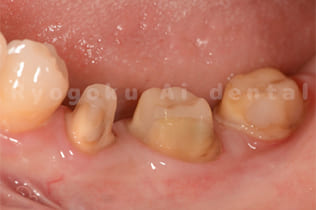

Case06

- 重度カリエス

- 治療期間

- 約2ヶ月(最終補綴装着まで含む)

- 治療内容

- クラウンレングスニング

- 治療費用

- 88,000円(2歯分)

他院で虫歯が大きく、抜歯を宣告された患者様です。歯茎に埋まっているところの虫歯を歯茎の位置を変えるクラウンレングスニングを行い、治療を行いました。痛みもなく、術後も良好です。